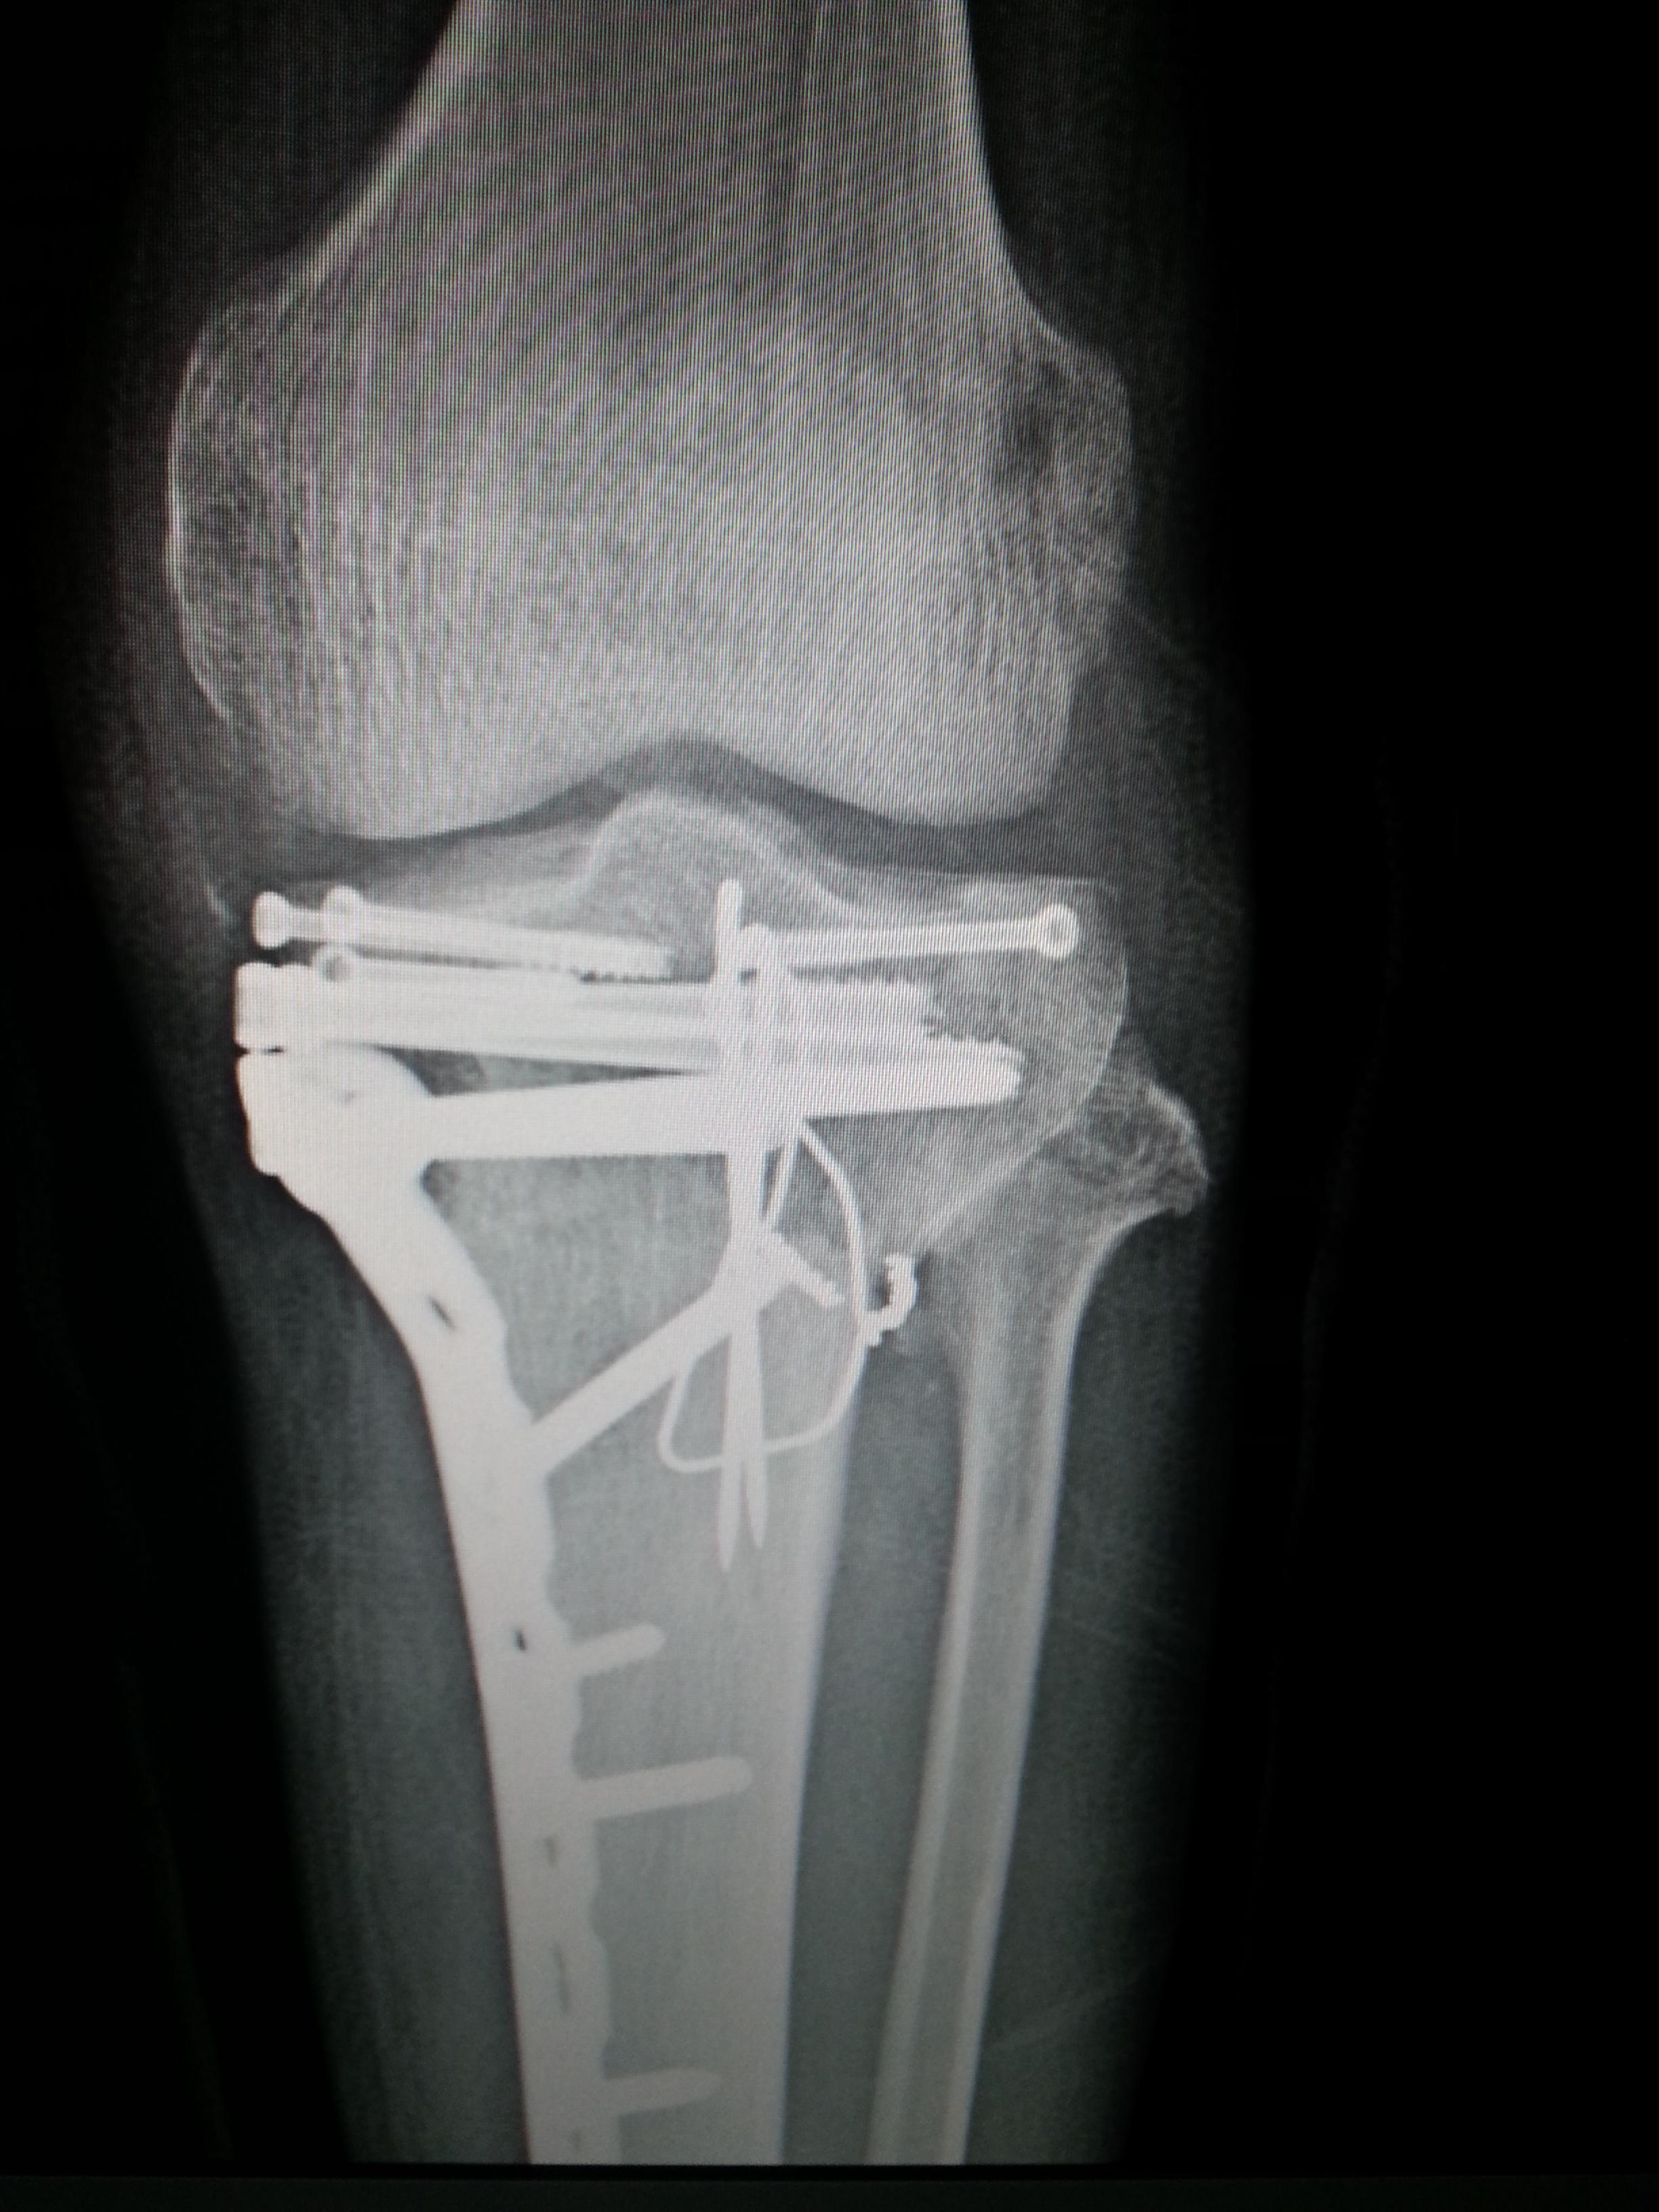

오토바이를 타고 가는데...배달하는 어린 아이가 나를 들이 받아서...

나는 그날 이후로 장애인이 되어 버렸다..

주요한건..오늘자..아직도 이 핀을 제거하지 못하고..

아직 정상적인 상태가 아니란것...